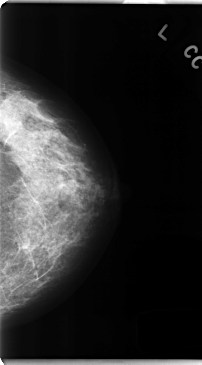

C_0162_1.LEFT_MLO

C_0162_1.LEFT_CC

LEFT_MLO LINES 4728 PIXELS_PER_LINE 2376 BITS_PER_PIXEL 12 RESOLUTION 50 NON_OVERLAY